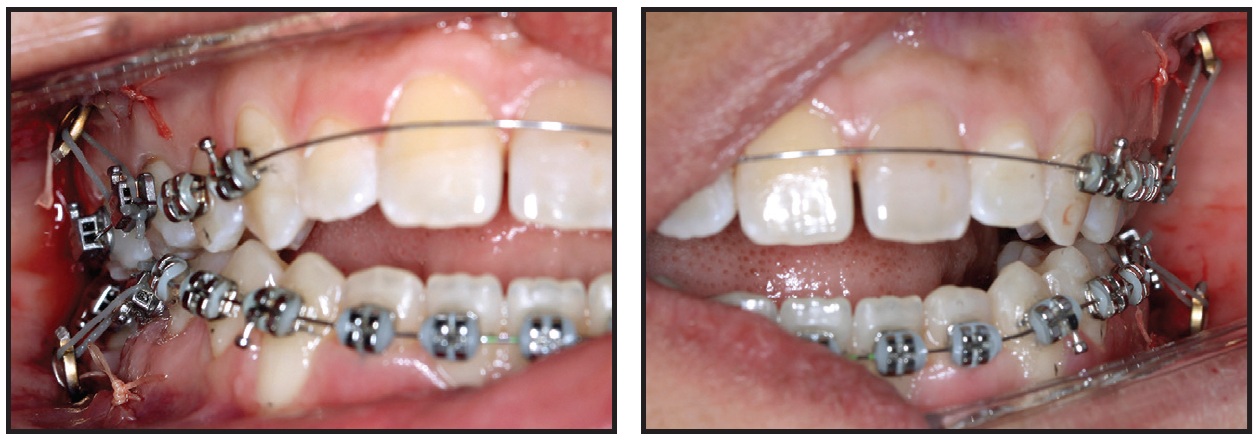

On the same day as the miniplate installation, orthodontic treatment began with placement of .018" × .028" Ricketts-prescription fixed appliances and .012" nickel titanium archwires in both arches (Fig. 5). The first molars were anchored to the miniplates with elastomeric ligatures. The upper central and lateral incisors were not included in the archwires while endodontic treatment of the central incisors was still in progress.

After 21 days of leveling and alignment, .016" × .016" Titanol* thermoactivated archwires (80g) were placed, followed by .016" × .022" thermoactivated wires (120g) in both arches (Fig. 6).

Fig. 5 Fixed appliances bonded on day of surgery; .012" nickel titanium archwires inserted and first molars anchored to miniplates with elastomeric ligatures.

Fig. 6 After 21 days of leveling and alignment.

The premolars were included in these mechanics, supported by the miniplate anchorage. Because of the more superior positioning of the upper miniplates and the more inferior positioning of the lower miniplates, with both placed posteriorly on the vestibular side, bone remodeling was achieved in three planes of space, producing simultaneous intrusion, distalization, and labial tipping forces.

Correction of the anterior open bite, with a slightly positive vertical overjet, was observed after three months of treatment (Fig. 7).

Fig. 7 After three months of treatment, showing correction of anterior open bite and buccal inclination of upper first molars as side effect of intrusive mechanics.